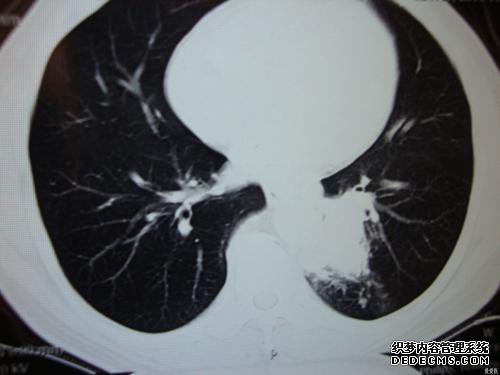

考虑到小叶性肺炎,对病史和其他临床试验的结果进行综合分析,通常采用抗生素进行抗生素治疗

首先要考虑的是肺炎,但应观察到阴影和其他硬化性病变(如结核和肿瘤)的具体位置和形状。

建议根据需要执行CT扫描以及改善和支气管镜检查。